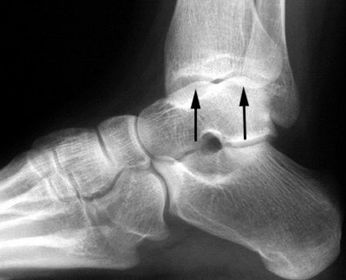

What disease is this? What does the arrow indicate? | Rheumatoid arthritis. Arrow = Bone erosion secondary to inflammation of retrocalcaneal bursa. |